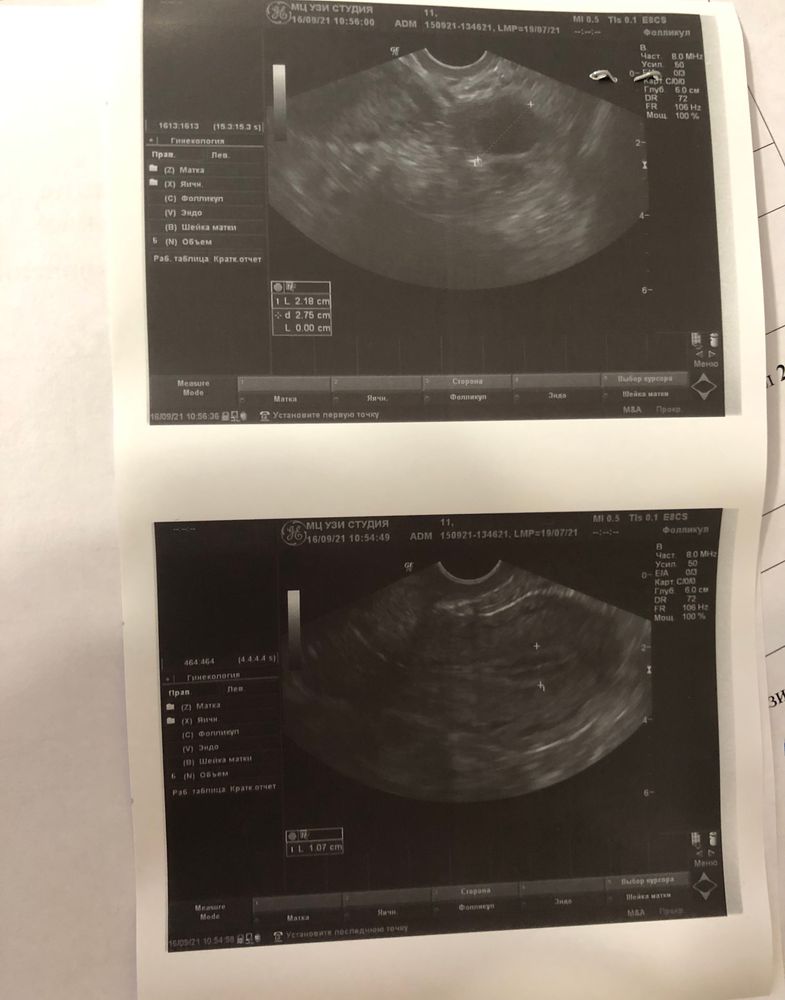

ОВУЛЯЦИЯ

Все замечательно, О вот-вот. На следующем УЗИ наверняка уже желтое тело будет)

Светлана Боровик, да,при таком в любой момент уже может.Но у вас рост за 2 дня всего 2,2 мм,поэтому может и больше дней понадобиться,а вы не знаете при каком размере у вас лопается?

Наталия Мечтаю о Дочке, при каком размере лопается не знаю 🤷🏼‍♀️